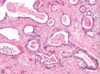

What is this showing?

- polyp

- 1st arrow is villus pushed to the side

- (epithelial)